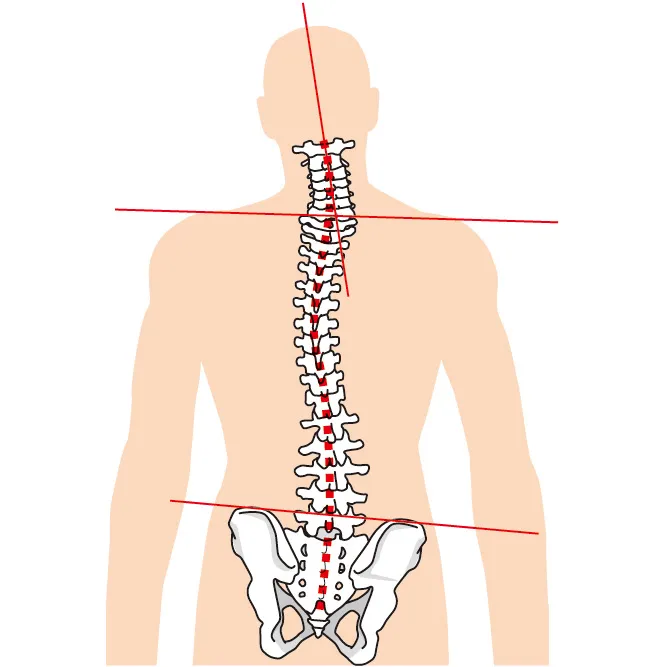

- 姿勢の崩れは背骨や骨盤にまで影響し、全身のバランスを乱す

背骨の歪みは内臓機能や代謝の低下、免疫力の低下にも影響

脊椎構造と顎の関係

- 頚椎(7個):首の部分で、顎と特に連動しやすい

- 胸椎(12個):背中の部分。呼吸や内臓機能とも関係

- 腰椎(5個):体幹の安定に関わり、顎のズレで負担が増加

- 仙椎・尾椎:骨盤や座位バランスに影響